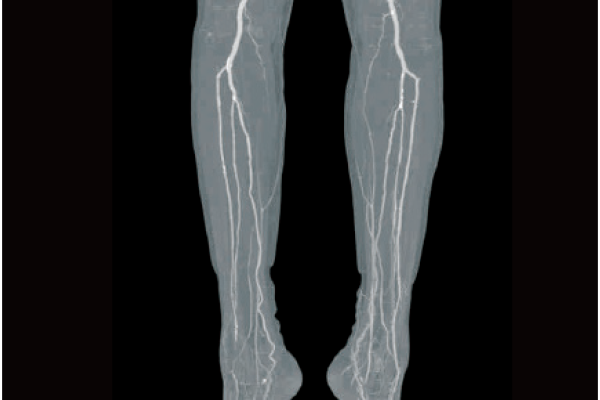

Based on the previously stored information, the areas recognized as blood vessels are extracted.

Vessels are extracted with one click by using image recognition technology.

Lower extremity bones removal